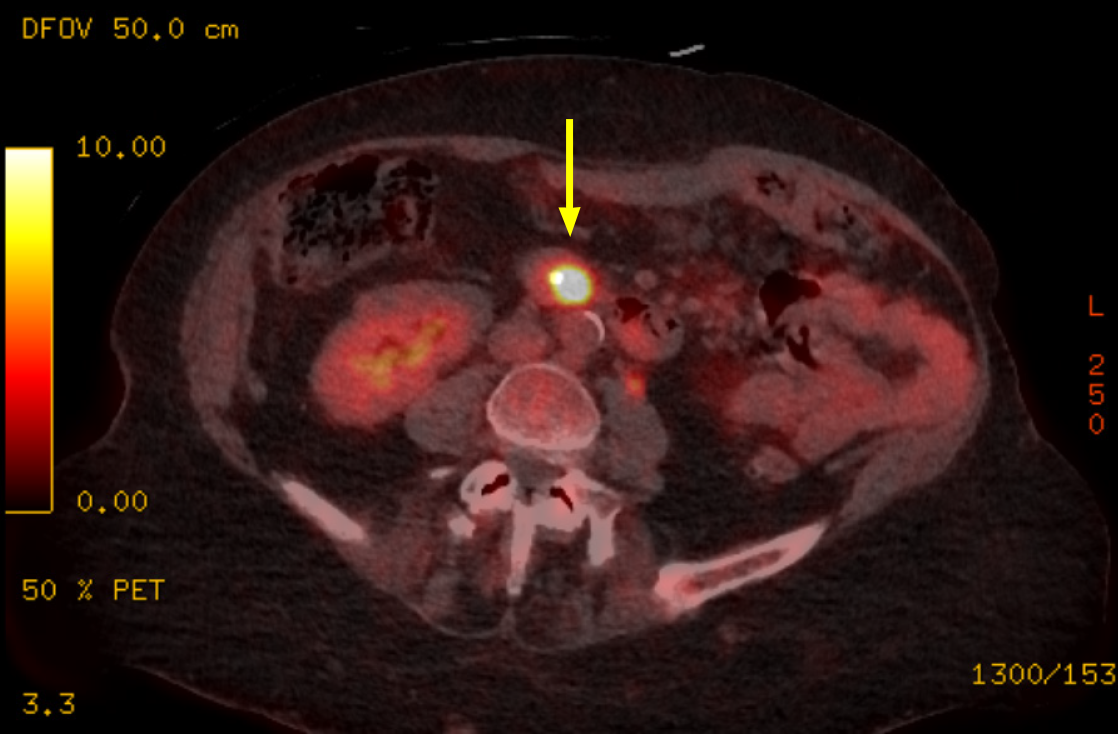

Contrast-enhanced computed tomography demonstrated dilated pancreatic duct measuring 9 mm with associated pancreatic parenchymal atrophy (Figure 1). Endoscopic visualisation of the ampullary lesion during ERCP was limited due to luminal collapse; a biliary stent was inserted. Positron emission tomography revealed no evidence of distant metastatic disease (Figure 2).